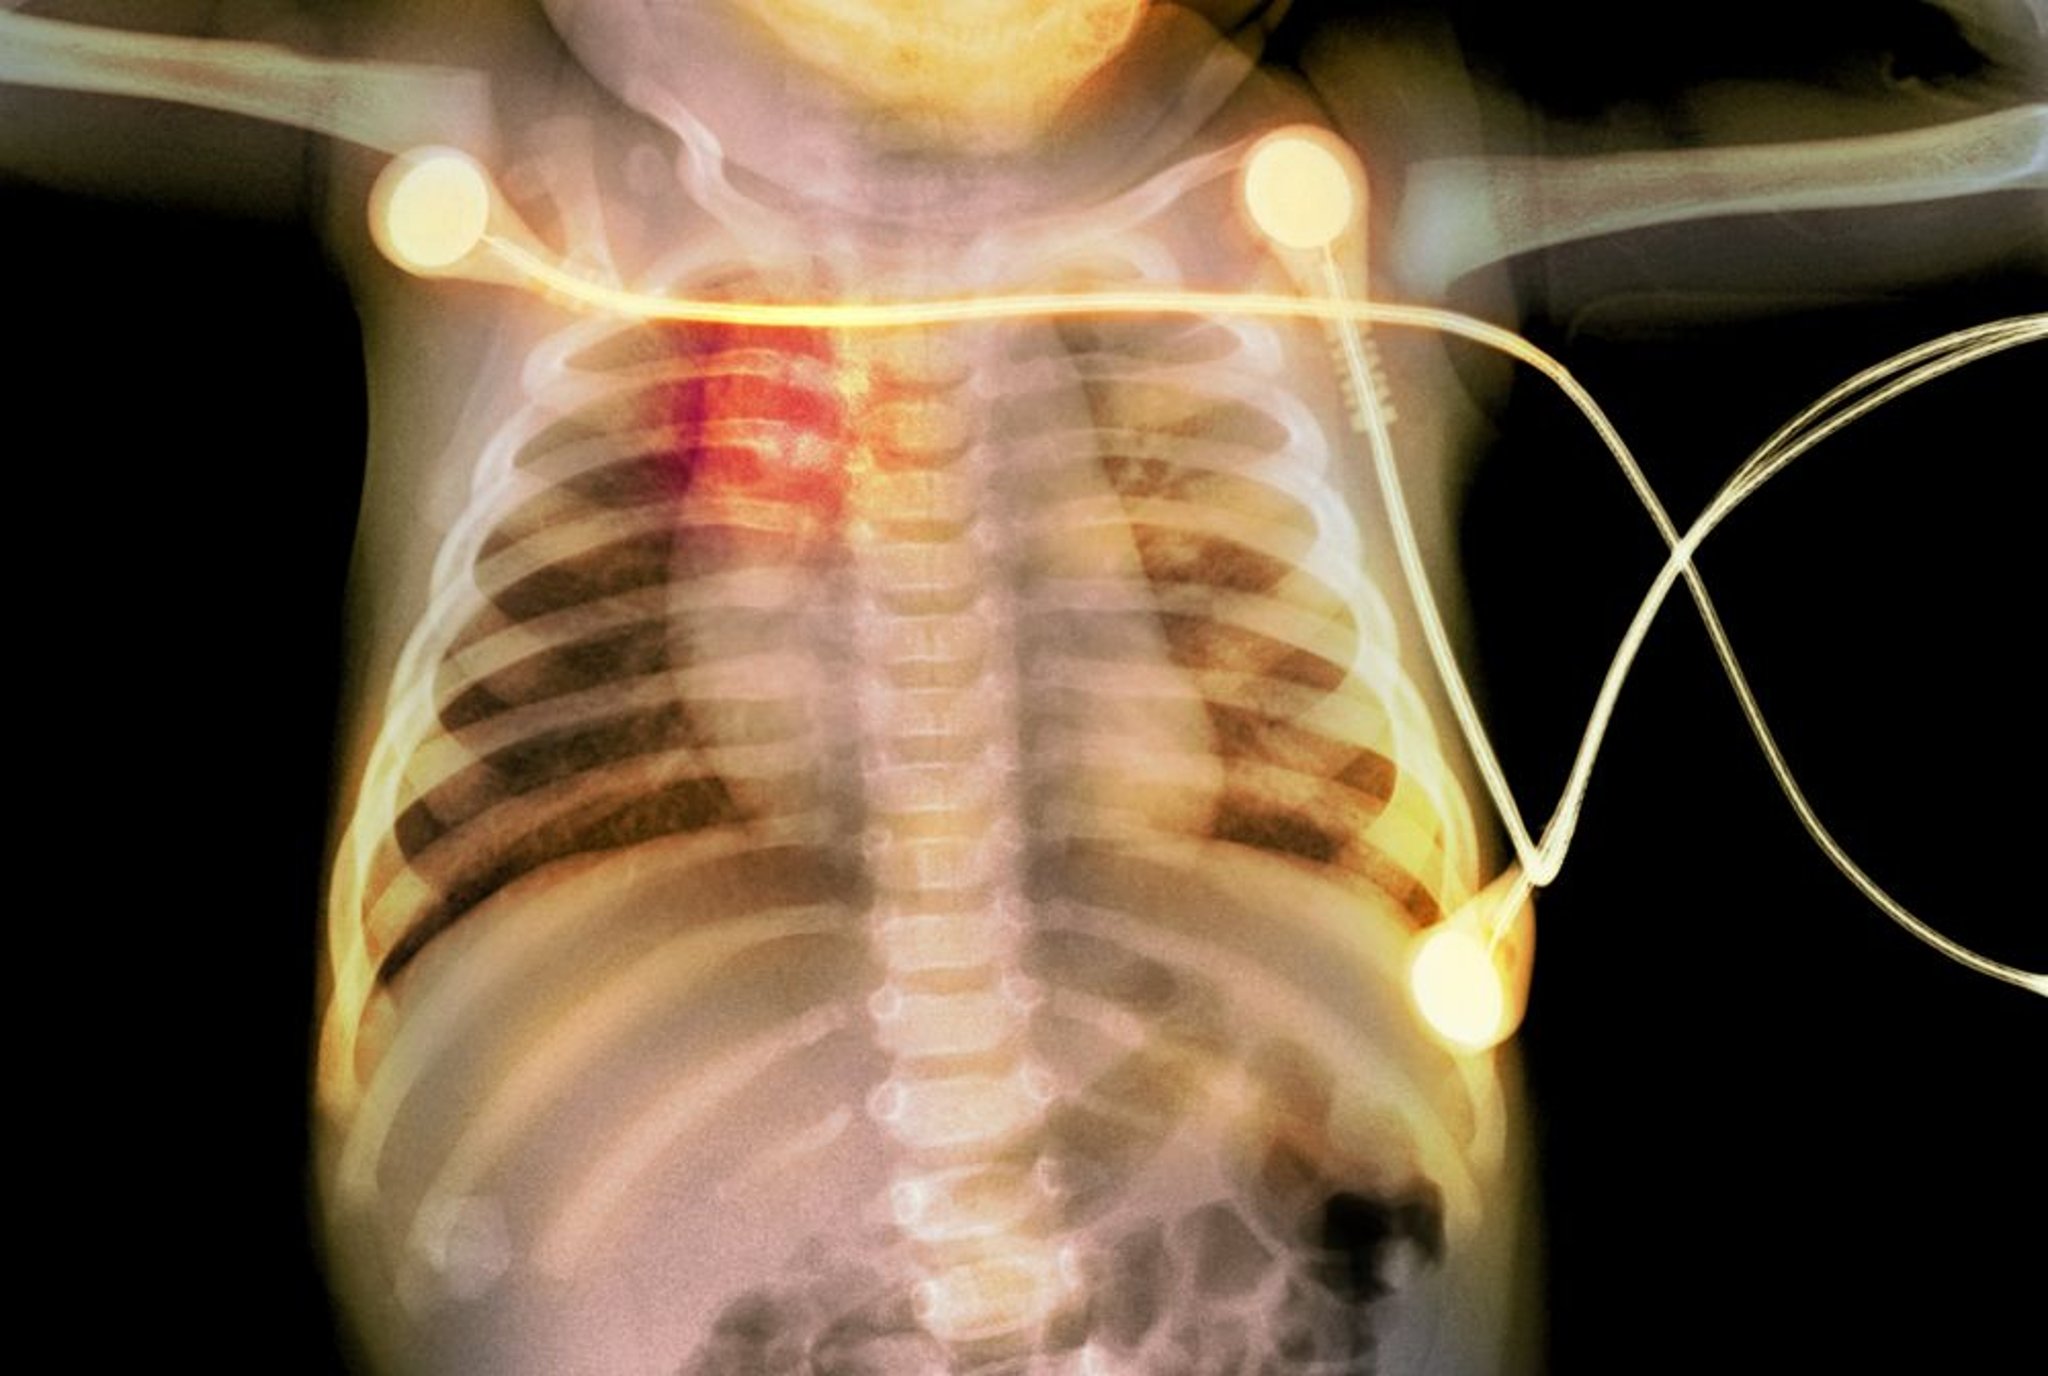

Fratture costali in un neonato

Questa radiografia mostra fratture costali (evidenziate in rosso) in un neonato, indicative di abusi sui minori.